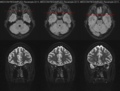

-

MRT des Sehnervs (axiale und koronale Schnittbilder)